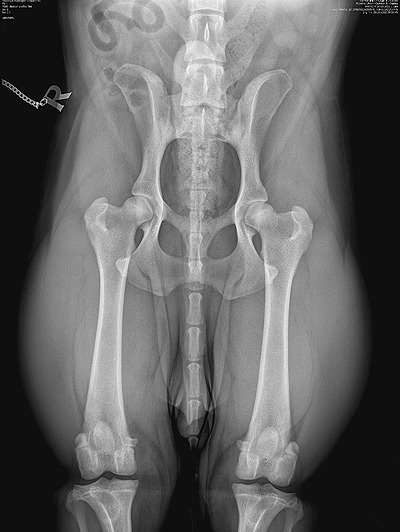

Röntgen-Gutachten X-ll-Wurf Von

meinem X-ll-Wurf (Finale ex Chelsea x

Juneau ex Chelsea) liegen die ersten fünf Röntgen-Gutachten der Hüft-

und Ellenbogengelenke vor. Beurteilt wurden die Röntgenaufnahmen durch

den vom LCD bestellten Gutachter Dr. Tassani-Prell. Ich freue mich sehr

mit den Eigentümern dieser fünf Hunde:

Xabi ex Chelsea: HD: B2/B2 und ED-Grad: 0/0 Xanto ex Chelsea: HD:

A2/A2 und ED-Grad: 0/0 Xello ex Chelsea: HD: B2/B1

und ED-Grad: 0/0 Xiao ex Chelsea: HD:

A2/A2

und ED-Grad: 0/0 Xena ex Chelsea: HD: C1/B1

und ED-Grad: 0/0 Xsara ex Chelsea: HD: A2/B1

und ED-Grad: 0/0. Auch Xenon &

Xiva wurden bereits untersucht, die offizielle Auswertung steht

allerdings noch aus.